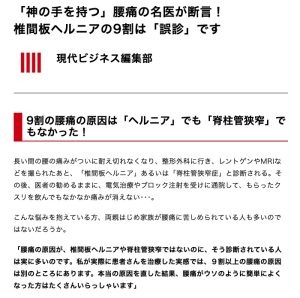

ヘルニアは誤診

少し前の現代ビジネスの記事ですが、『椎間板ヘルニアの9割は「誤診」です』という記事があったり書籍がでたりしていましたが、納得できる部分が多々あります。

専門知識と経験豊富なドクターによってヘルニアと診断されている方の9割が慢性腰痛の原因とヘルニアは関係が無いと確認されています。

しかし軟骨の突出したヘルニア状態が《本当の痛みの原因では無い》場合も多々あります。割合で言うと9割強です。信じられないかも知れませんが慢性的な腰痛でヘルニアと診断された方々の100人中90人が痛みの原因とヘルニアの関連が無いのです。